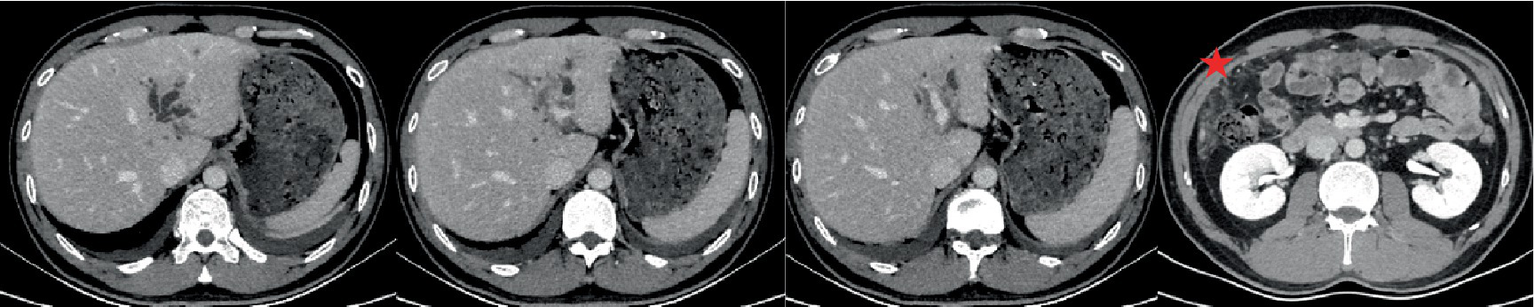

Computed tomography (CT) and magnetic resonance imaging (MRI) of the upper abdomen revealed the presence of multiple lesions in the longitudinal fissure of the liver, hepatic hilum and omentum (Figure 1).

Figure 1

Abdominal non-contrast-enhanced computed tomography (NECT) and contrast-enhanced computed tomography (CECT; A: Artery phase, P: Portal vein phase, V: Vein phase) revealed mild dilatation of the bile ducts in the left lobe of the liver. Additionally, low-density areas (indicated by an arrow) were observed along the hepatic longitudinal fissure, extending toward the hepatic hilum. The boundary of these inflammatory areas appeared unclear, accompanied by narrowing and indistinctness of the adjacent left branch of the portal vein. Inflammatory exudation was also present in front of the colon. Moreover, there was thickening of the peritoneum and omentum. During CECT scans, the lesions exhibited gradual and significant enhancement, displaying a consistent and uniform enhancement pattern. However, the density of the lesions at each stage was lower compared to that of the liver parenchyma. Abdominal non-contrast-enhanced MRI (NEMR) and contrast-enhanced MRI (CEMR; A: Artery phase, P: Portal vein phase, V: Vein phase) demonstrated that the inflammatory areas in Segment 3, near the hepatic hilum, appeared as areas with low signals on T1-weighted imaging and high signals on T2-weighted imaging. On diffusion-weighted imaging (b = 800), limited diffusion was observed within the lesions (indicated by a triangle). These lesions measured approximately 3.6 cm × 3.8 cm and displayed a crab-like edge, distinctly separate from the hilar bile duct and blood vessels. Regarding contrast enhancement, the lesions exhibited moderate progressive enhancement on CEMR. Furthermore, lymph nodes in the hilar region were found to have distinct and uniform enhancement on CEMR.